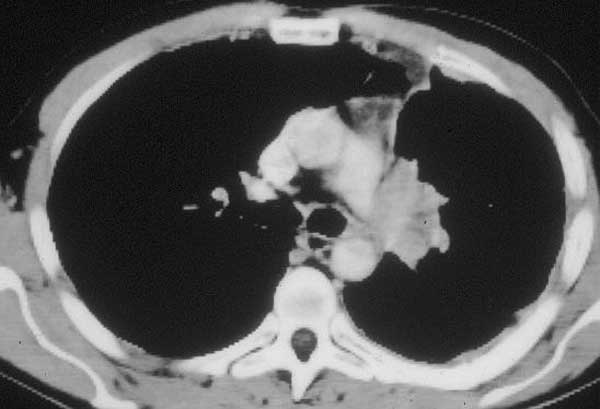

This technique is very versatile and can be used in a variety of circumstances. These range from limited infiltration involving the origin of segmental arteries to large defects extended longitudinally on the PA (Figures 8, 9). The only necessary condition is that the opposite side of the circumference of the PA is free from tumor.

![]() |

| Figure 9: Line drawing (left) and intraoperative image (right) showing the usual pattern of infiltration of the interlobar portion of the pulmonary artery posterior to the left upper lobe bronchus.* | |